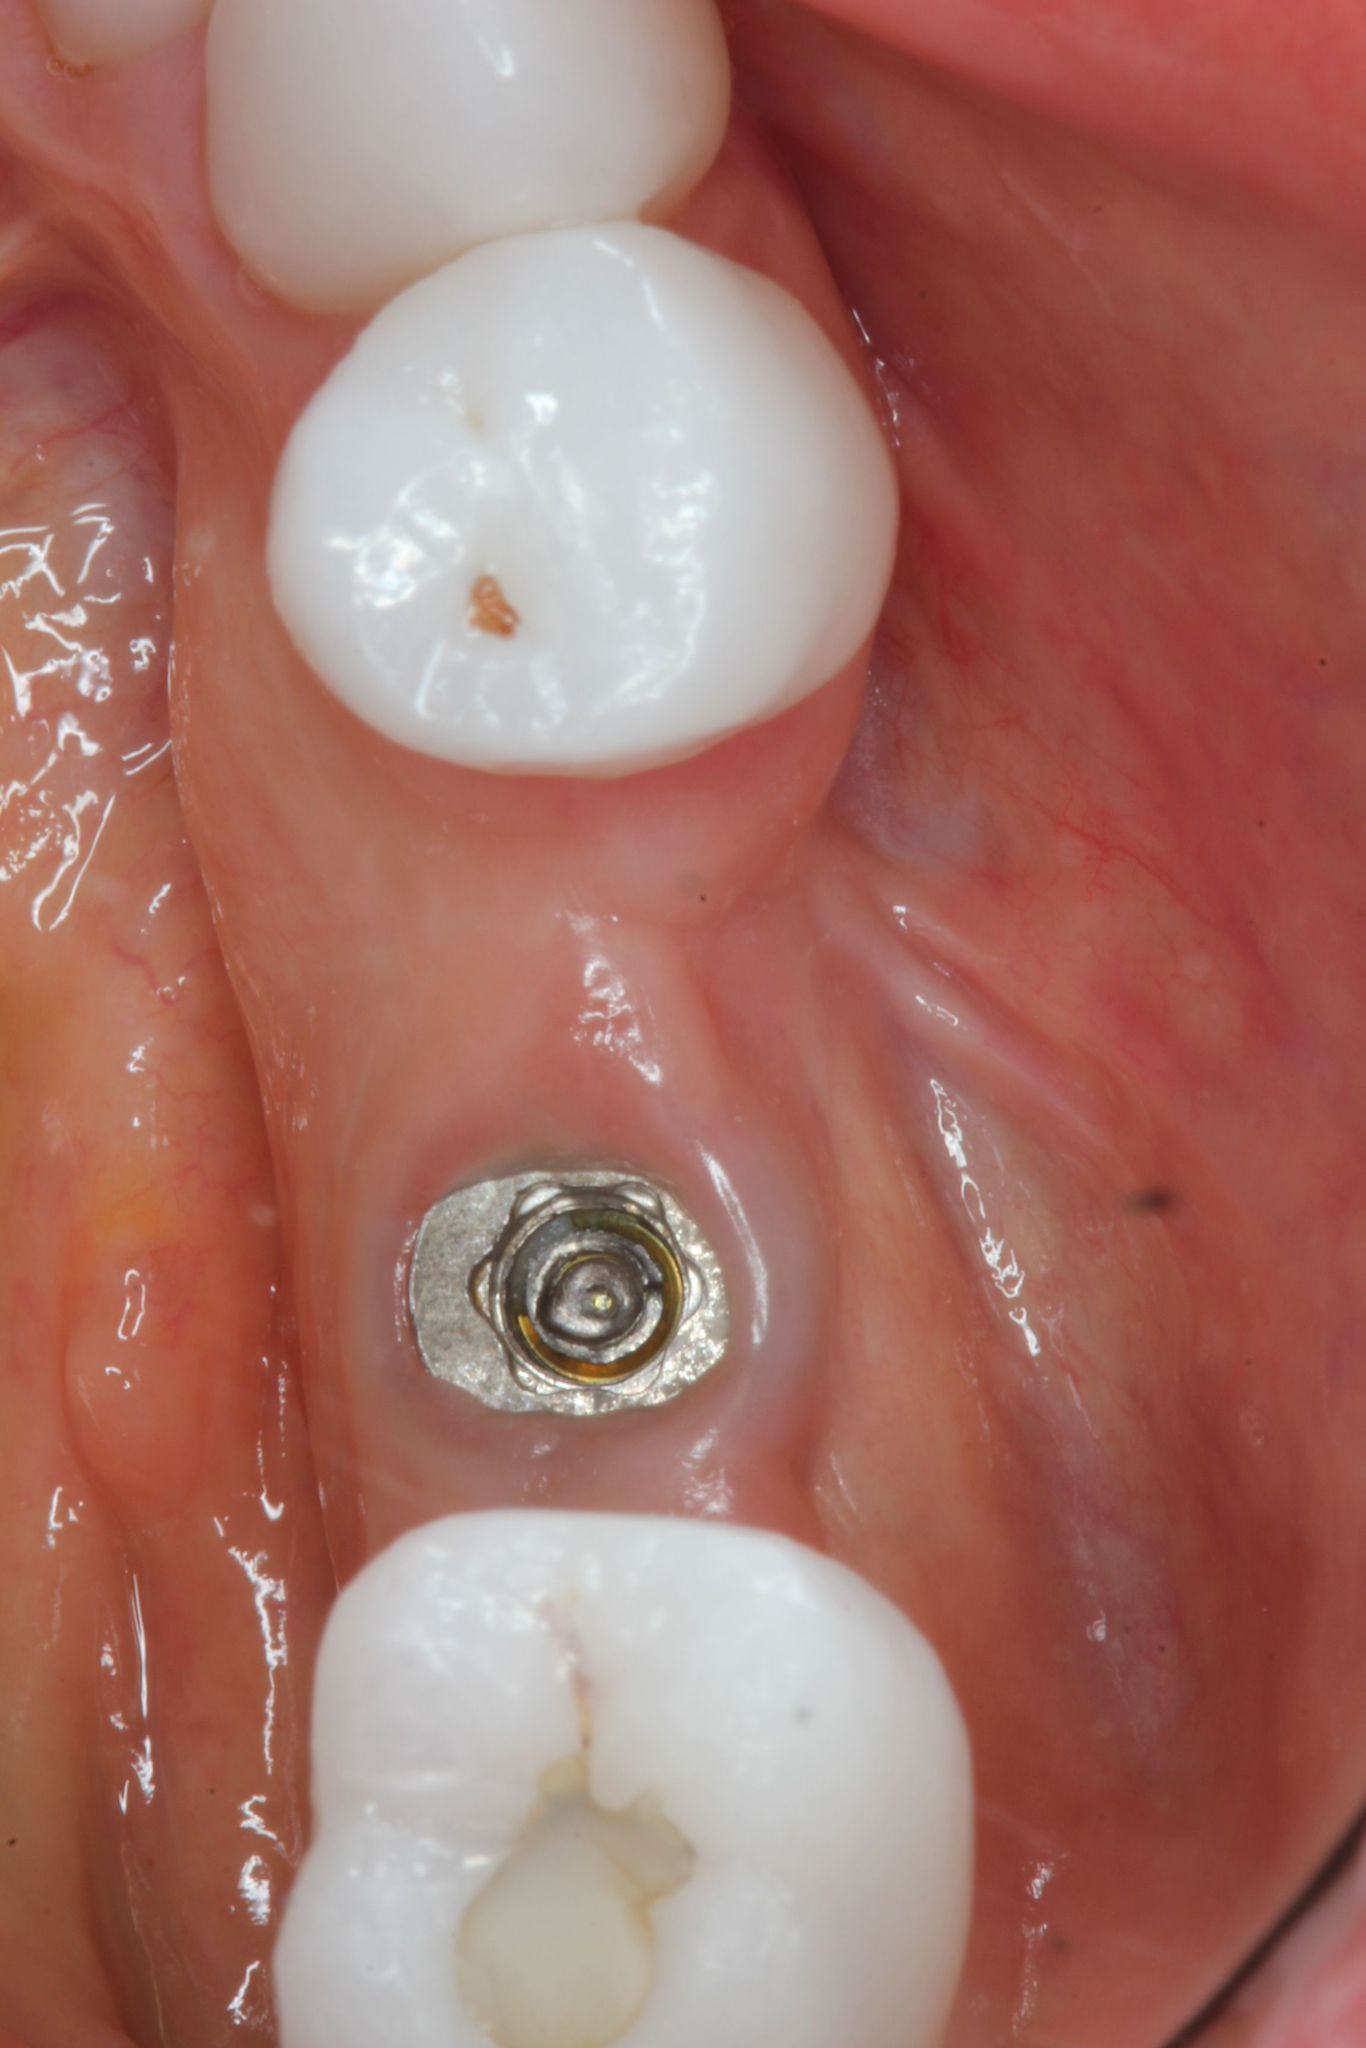

Removing a Broken Abutment Screw

Dr Sascha Jovanovic

What to do when your patient arrives in your office with panic in their eyes and the implant crown in their hands?Repairing a broken dental implant abutment screw requires careful handling and attention to detail. Here are t...